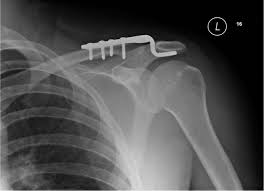

Hình ảnh kết hợp xương khớp cùng đòn bằng nẹp móc

Phương pháp kết hợp xương bằng nẹp móc nhanh gọn, dễ thực hiện. Nhược điểm là chi phí cao và bệnh nhân thường than phiền đau tại vị trí bắt nẹp, hoặc hội chứng chạm.

Phương pháp này chỉ sử dụng cho trật khớp cùng đòn cấp tính (dưới 3 tuần).